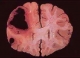

在超高倍的电子显微镜下,通过对末梢血的观察,可以明显看到胆固醇的结晶和乳糜颗粒,有的患者还出现大块的斑块,这些胆固醇结晶和脂质斑块黏附在血管内壁,即可形成脂质血栓,高脂血症是形成脂质血栓的主要原因。